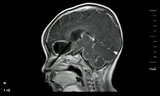

Hình ảnh trên phim chụp cho thấy cây kim ở trong đầu bệnh nhân. Ảnh: SCMP.

Các bác sĩ tại một bệnh viện ở thành phố Lạc Dương, tỉnh Hà Nam, lấy ra chiếc kim gỉ dài 6 cm trong đầu bà Wang Xiaohong, 58 tuổi, Dahe Daily đưa tin hôm 26/9. Vật thể lạ là nguyên nhân khiến bà Wang bị đau đầu suốt nhiều năm qua.

Bà Wang cũng bị động kinh và không biết đến sự tồn tại của chiếc kim, cho tới khi chụp tia X.